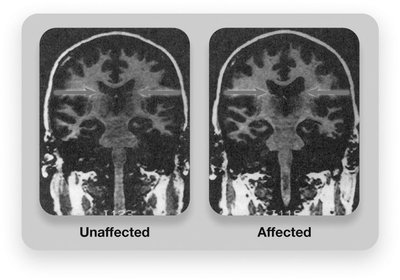

Biological findings include larger brain ventricles, reduced frontal lobe activity, and neurotransmitter imbalances (dopamine overactivity, glutamate underactivity). Environmental risk factors include extreme stress, low socioeconomic status, minority status, prenatal environment, and cannabis use.